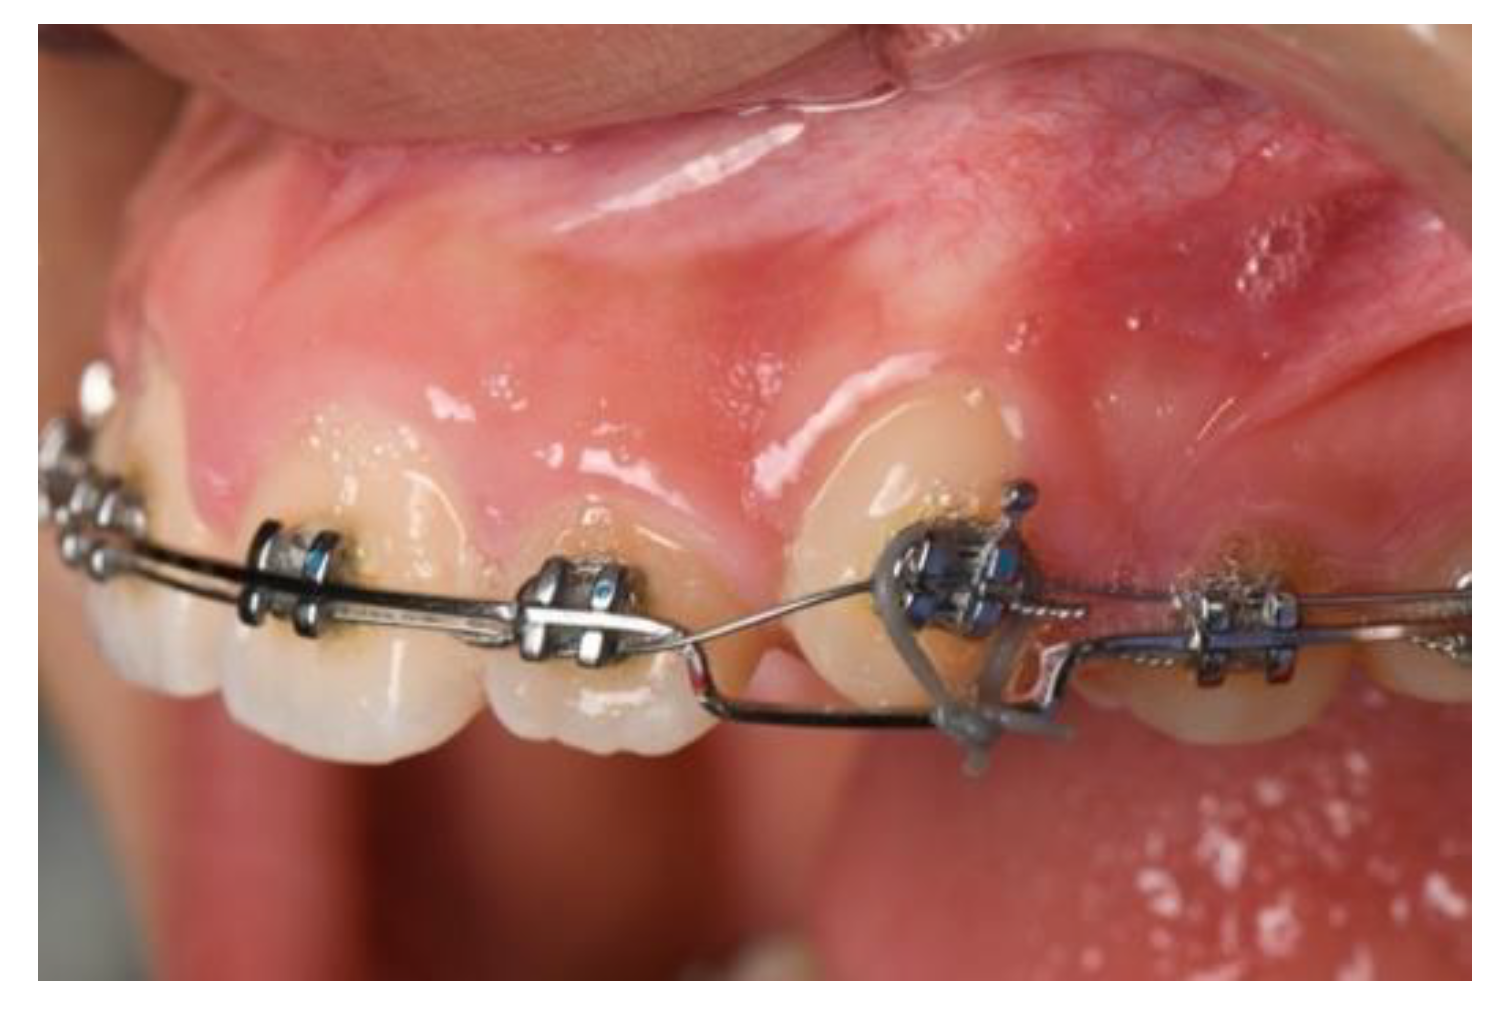

2.1. Ferrule/Crown Lengthening

5. Conclusions